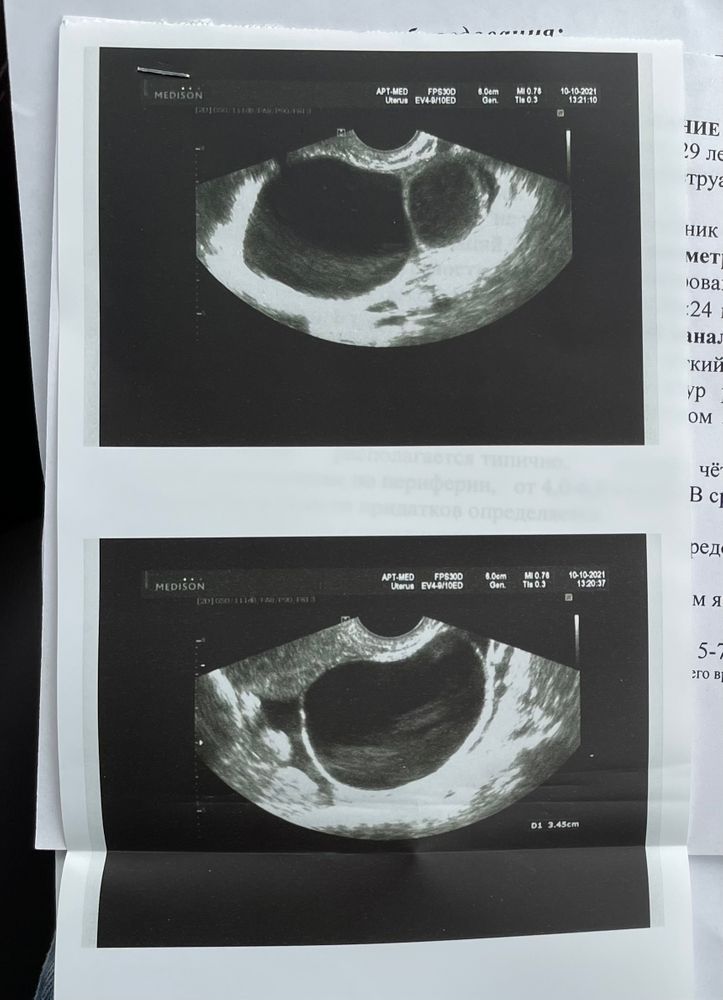

девочки, подскажите , пожалуйста. Впервые за всю жизнь у меня появилась киста таких размеров 5 см( раньше была 2 мм и то 1 раз). Всегда цикл где-то 26 дней, овуляция на 12 день, проводила тесты на 12,13,14 овуляции не было , ну и я потом забила , решила сходить на 26 день цикла проверить была ли овуляция , а нашли кисту, да ещё и не одну! Вторая узисты пока разводят руками и лишь предполагают что это ЖТ. С мужем планируем, вот мне интересно овуляция могла быть попозже из-за этого ? Стоит ли мне питать надежды на беременность, сейчас второй день задержки, но при такой кисте это нормально вроде. Тесты только клиаблю слегка полосатят, но они и так часто реагентят. На фото узи позавчера

Ирина, я буду рада любому исходу событий 😂я уже жду месячных как никогда, потому что мечтаю, чтобы они быстрее рассосались , чтобы нормально заниматься спортом!но эти узисты и врачи говорят, что даже Б исключить нельзя, и даже врач сказала, что это похоже на ЖТ…. Вблизи на фото чуть другая структура там

Ксюша, как по мне - они идентичны у вас на фото и это оба фолликулы, фолликул на узи имеет чёткие границы и внутри как бы чёрное пространство. 5 лет стажа планирования и моя любимая узистка мне показывала и рассказывала как и что)) у меня качество не такое хорошее, но вот на одном фото фолликул 13 мм и жёлтое тело 17мм, жёлтое тело совсем другой консистенции